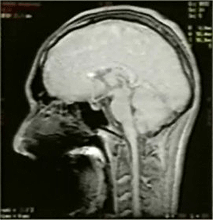

<口腔内のキーパーのMRI画像への影響>

キーパー部近傍(5cm未満)のMRI診断は困難になります。このキーパー部近傍の診断が必要な場合、MRI診断を行う医師よりキーパーの撤去を要求されることがありますので、患者への充分な説明を行ってください。

キーパーなし キーパーあり